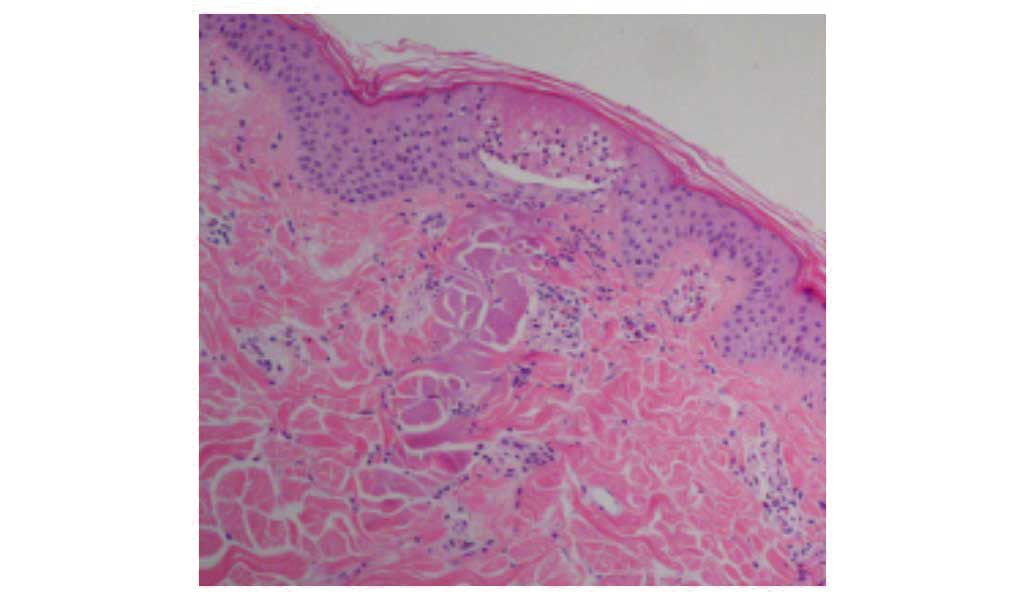

フラクショナルレーザーとは、一定の間隔で皮膚に小さな点状の穴をあけるレーザーです。 レーザー照射した部分の組織を剥がれることで、創傷治癒力により、新しい皮膚へ再生、ターンオーバーを促進させます。 エルビウムヤグレーザーによるフラクショナルレーザーは、表皮から真皮までの様々なお悩み対し幅広く対応することができます。

傷の治りが早い(治癒期間が短い)仕上がりがきれい。 周囲の正常組織への熱損傷がほとんどないため、施術後の赤みや色素沈着のリスクが軽減される。

従来のレーザー治療がターゲット全面へ照射するのに対し、フラクショナルレーザーは点状にレーザービームを照射を行います。

フラクショナルレーザーは、CO2フラクショナルレーザーに比べ、凝固層がほとんどない治療(蒸散)が可能です。